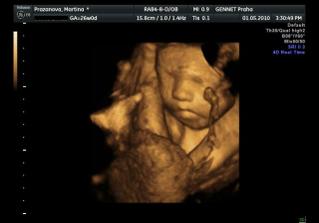

Určitě dám sem vědět i s aktuální fotečkou. Jména mám v pase. A 1.května jdeme na 4D UTZ, tak se moc těšíme 🙂

Letí to jak blázen, vždyť to znáš 🙂. Zatím nevíme nic, ale zítra jdeme na velký genetický UTZ, tak snad tam prcek nebude sedět v tureckém sedě jako minule 🙂))